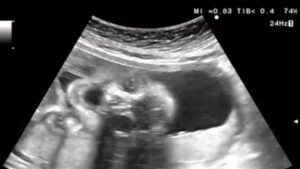

妊娠22週4日のエコー検査の際、画面に映し出された赤ちゃんはあくびをしていました。

エコー中は毎回元気に動き回っていることが多かったのですが、最後に大あくびを見せた赤ちゃんに、先生もママさんも「元気すぎるくらいだね」と笑ってしまったそうです。